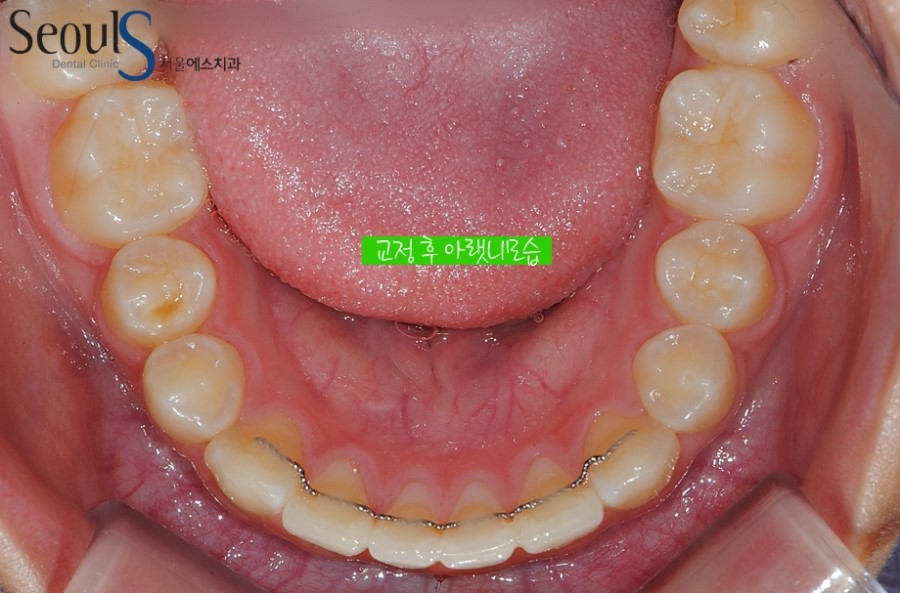

교정 후 아랫니 모습입니다

아랫니 역시 예쁘게 교정 된 모습입니다